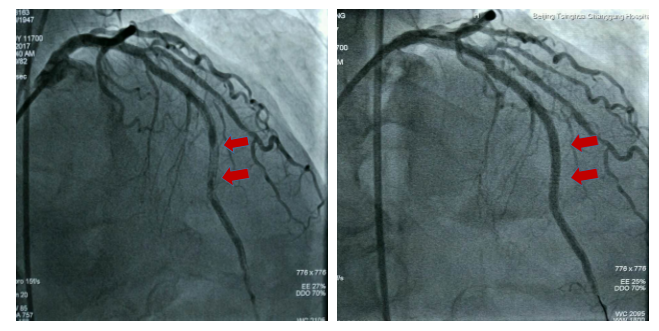

图3 激光消蚀术前及术后的冠脉造影结果对比

准分子激光是一类脉冲气体激光,混合惰性气体与卤素元素(如XeCl)作为活性介质以产生短波长、高能量的紫外线(UV)脉冲光源。激光穿透深度与波长直接相关,采用UV激光(更短的波长308nm)拥有更浅的穿透深度(<50μm)、释放更小的热量以及更少的不必要的组织损伤,确保安全性。被俗称为“冷激光”。准分子激光组织消融由三种不同机制介导:光化学效应、光热效应以及光机械效应。紫外线激光光线被血管内物质吸收并破坏碳-碳双键(光化学效应),这使得细胞内液温度升高,从而导致细胞破裂并在导管前端产生蒸汽气泡(光热效应),这些气泡的膨胀和暴缩瓦解了血管内的阻塞成分(光机械效应),释放的碎片直径小于10μm,它们可被网状内皮系统所吸收从而避免微血管的阻塞。紫外光源穿透组织并产生蒸汽气泡所需要的阈值量称之为“能量密度”(30~80 mJ/mm²)。1秒内脉冲激发次数“脉冲频率”。每次脉冲的持续时间叫做“脉冲持续时间”即脉宽(通常不超过125ns)。根据病变斑块性质,选择合适的能量密度及脉冲频率。在我们这个病例中采用能量30mJ/mm²、频率40Hz以及40mJ/mm²,频率40Hz行斑块共消蚀2次,球囊即可顺利通过病变完成后扩张,并最终应用血管内超声(IVUS)精准评估手术后效果。